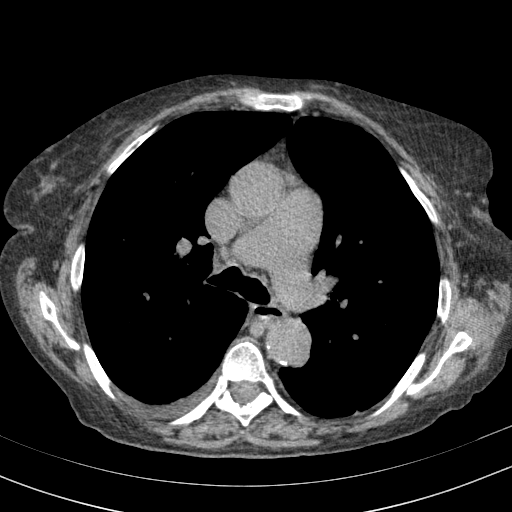

Original VENOUS CT scan

Full window (WL 1023.5, WW 4095 β†’ Low βˆ’1024, High +3071)

Actual HU range: [-160.0, 240.0]